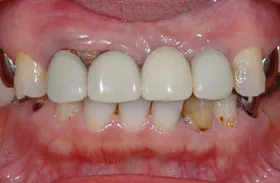

■治療前:奥歯が無いため噛み合わせが深く下の歯が全く見えない

噛み合わせが低いため全体的に歯が削れている

■治療後:下顎 左下5・6番、右下4・6番にインプラント治療

その他の歯に補綴治療をしたことにより、奥歯もしっかりと咬むことができ、奥歯ができたことにより噛み合わせも上がって下の歯も見えるようになり、審美的にも改善された

| 主訴 | 歯科治療をしても歯がすぐに欠けてしまう 奥歯が無いため、奥歯で咬めない |

| 治療方法 | インプラント治療 + 補綴治療 |

| 治療期間 | 約1年 |

| 通院回数等 | 約20回 |

| 費用 | 約250万円(税込) |

| リスク・副作用 | 術後の腫れ・痛み |